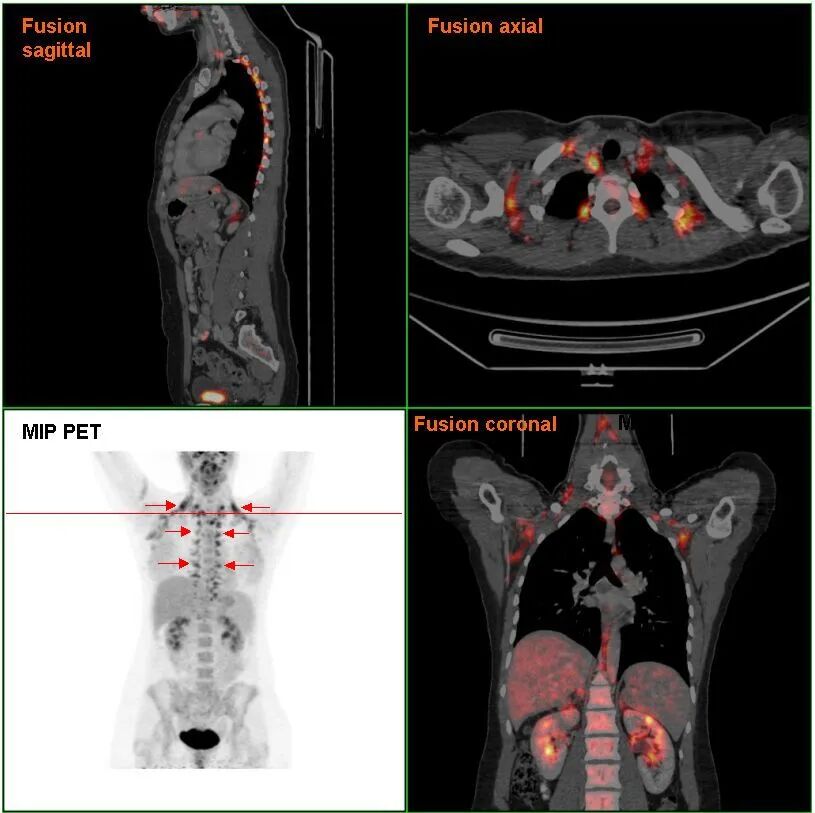

此前很长一段时间里,人们一直认为棕色脂肪只存在于新生儿中,用来维持体温,随着幼儿或幼崽成年便会消失不见。直到2009年,科学家让一些健康的成年受试者在热中性(thermo-neutral)条件下或暴露于寒冷环境中几个小时后,接受正电子发射断层扫描(PET)-计算机断层扫描(CT),才意识到冷环境诱导产生了棕色脂肪,且它们出现在人体颈部区域。后来,科恩和同事通过研究证实,棕色脂肪会随年龄增加而减少,在超重和肥胖者身上不太常见。

沃尔夫鲁姆与来自苏黎世大学医院的同事一起分析了该医学在2007-2015年间收集的、约8440名成年患者的正电子发射断层扫描-计算机断层扫描图像,注意到相较于1月至6月出生的人(意味着受孕时间是在一年内温度较高的季节),7月至11月出生的人(意味着受孕时间是在一年内温度较低的季节)的棕色脂肪组织活性显著更高。也就是说,受孕前的环境温度与棕色脂肪细胞的活性之间存在相关性。

棕色脂肪组织的PET-CT图像。图片来源:wikimedia commons/public domain